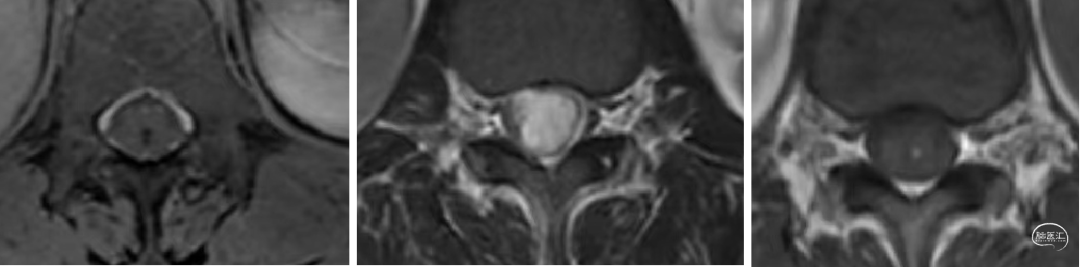

辅助检查:腰椎CT和MR示:L1-2椎管内硬膜下见一软组织信号结节,大小约24mm×12mm×10mm,T1W1低信号,T2W1稍高信号,增强扫描明显强化,但欠均匀,临近脊髓受压改变等。

术前腰椎CT和MR如下: